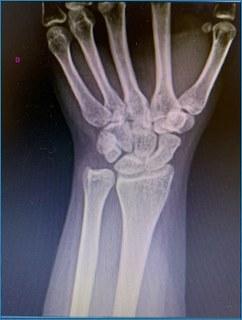

Visualizando a radiografia abaixo, a estrutura da mão que pode estar lesionada após trauma e ser responsável pela fisiopatologia do dedo em botoeira é:

Qual estrutura foi lesionada?

DBanda central